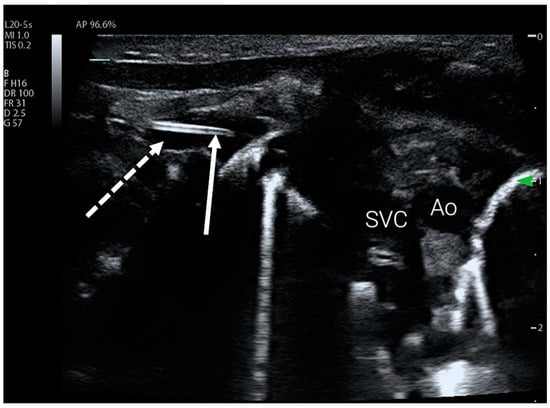

For upper limb PICC access, the protocol uses a subclavicular view to visualise the mediastinum and the subclavian vein (Figure 2). This acoustic window is also easy to obtain and has the advantage of visualising the venous junction between the subclavian vein and the superior vena cava (SVC), which is the innominate vein. If the catheter was not visualised, a view through the axillary fossa was obtained using either a linear or curvilinear transducer to visualise the axillary vein and the distal part of the subclavian vein. Failure to visualise the catheter using this view was considered an indication of malposition or inadequate catheter length. If the catheter was visible within the subclavian vein but its tip was difficult to visualise, the protocol required the user to obtain a simple transverse view of the jugular vessels and the contralateral subclavian vein to rule out tip position in these vessels.

Figure 2.

PICC catheter tip visible in the subclavian vein using subclavian view. The subclavian vein is marked with a dotted arrow, full arrow indicates catheter tip. Ao—aorta, SVC—superior vena cava.